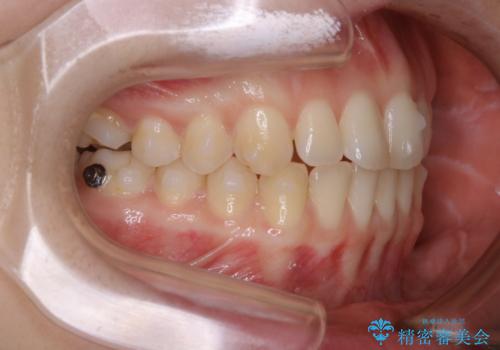

- 上下前歯のがたつきが気になるとご相談にいらした方です。

一見前歯のがたつきだけ改善させれば良い様に見えますが、このがたつきの原因は奥歯の嚙み合わせのズレからくるものであったため、インビザラインFULLで噛み合わせの改善から行っていきました。前歯の角度も改善されたために頑張って唇を閉じる必要がなくなり、横顔のシルエットも綺麗になりました。